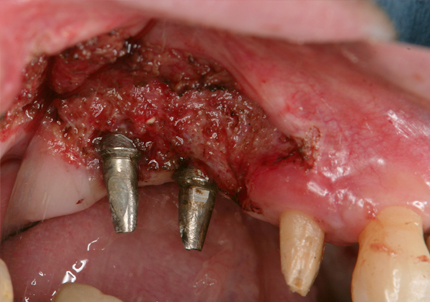

2.右側上顎洞サイナスリフト後にインプラント埋入

↑ サイナスリフト術前

↑ サイナスリフト術後

↑ 右上サイナスリフト後にインプラント埋入